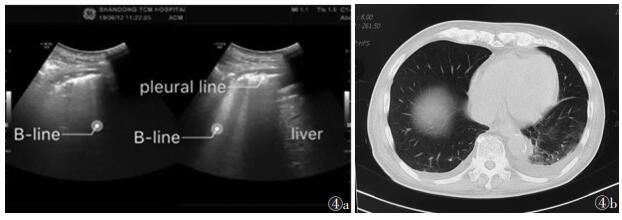

2 急诊与ICU常见肺部疾病超声表现 2.1 肺炎肺炎病理分期包括充血水肿期、红色肝样变期、灰色肝样变期、溶解消散期。肺炎充血水肿期,大多数肺泡含气良好,故声像图上一般不能显示病变。当病变进展至实变期时,声像图上表现为A线消失、B线出现(图 4)。若病情继续发展,肺泡内以组织的水肿增厚及渗出物的蓄积为主要病理改变时,声像图上表现为低回声肺实变,可伴动态支气管充气征;病变累及胸膜时,可导致胸膜增厚。病情恢复时,肺实变范围减小,肺间质综合征程度减轻,A线出现。若病情进一步发展,出现纤维组织增生,支气管、细小支气管受损阻塞,可导致完全阻塞性肺不张,表现为肺实变伴静态支气管充气征。由于各肺野病情进展不一,同一患者可同时出现各期超声表现[20]。

![]() |

| 图 4 男,79 岁,因胃间质瘤术后7 年,左上腹疼痛 1 个月余,乏力加重 1 周入院 图 4a 肺部超声示:胸膜线不规则增厚;可见数条B 线,肺间质综合征;双肺下叶肺炎可能,右肺明显;双侧胸腔积液(pleural line,胸膜线;liver,肝脏)图 4b 胸部 CT 示双肺下叶炎症病变,双侧胸腔及左侧叶间积液,胸壁水肿 |